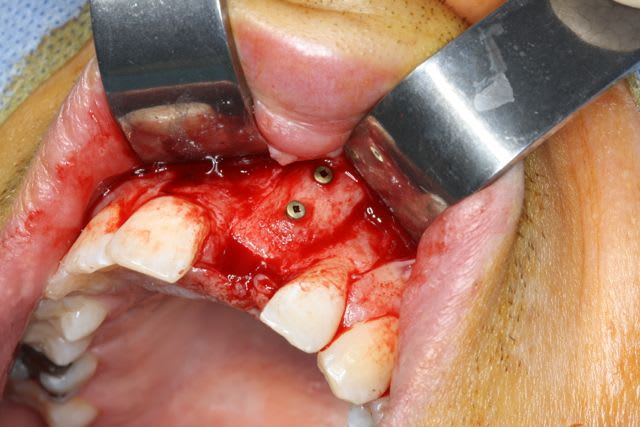

faux ils se résorbent beaucoup plus s'ils sont épais. J'ai des cas ou la tête de la vis de fixation qui était enfui dans la cuvette créée à la fraise boule apparait à 5 mois à 2 bon mm de la greffe.

ton bloc a été mis en dehors de l'espace osseux normal pour ce patient, il est au niveau gingivale des dents adjacentes.un remodelage naturelle s'en suit.

Photo d'un cas fait la sem passée, gain de 5-6 mm en vestibulaire (sur 12 mm) particules allogènes, en 4 mois.